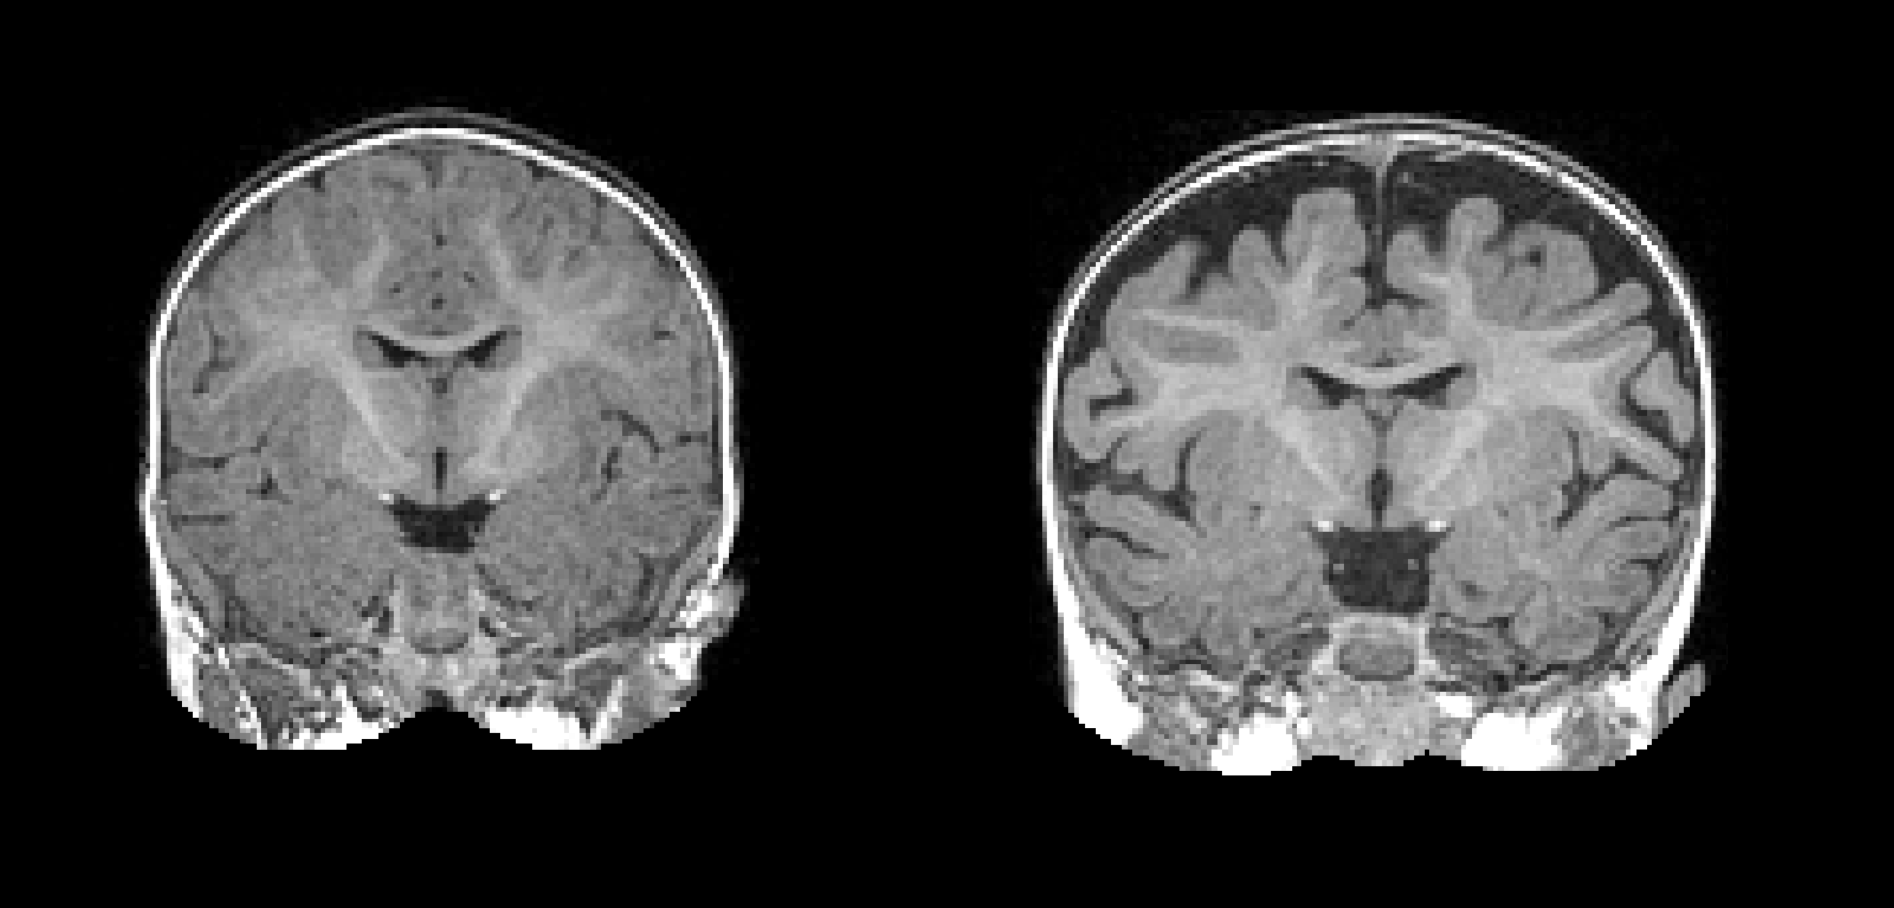

Earlier findings from the Infant Brain Imaging Study revealed that white fiber tracts grew at a slower rate in infants with autism compared to those who did not. While interesting, those findings were also preliminary. This year, a more detailed analysis of growth in infants with autism showed that increased surface area of the cortex from 6-12 months was tied to brain overgrowth at 12-18 months, which was then associated with social deficits62. The researchers then took this larger data set—MRIs of brain volume, surface area, cortical thickness at 6 and 12 months of age, and gender of the infants—and used a computer program to identify a way to classify babies most likely to meet criteria for autism at 24 months of age62. Now scientists are even closer to finding a biological method of detecting autism even before behavioral features emerge in babies with an older sibling with autism.

Credit: Mark Shen, University of North Carolina at Chapel Hill

This finding was followed by the discovery in the same dataset of the use of 6 months functional connectivity as an accurate predictor of autism diagnosis63 and identification of the circuit that controls a key feature of autism—joint attention64. Functional connectivity analyses at 6 months also revealed a different circuit for the emergence of repetitive behaviors and sensory sensitivities65. Later in the year, another analysis of the data revealed an 18% increase in cerebrospinal fluid outside the brain could be detected in those with autism as early as six months of age66.